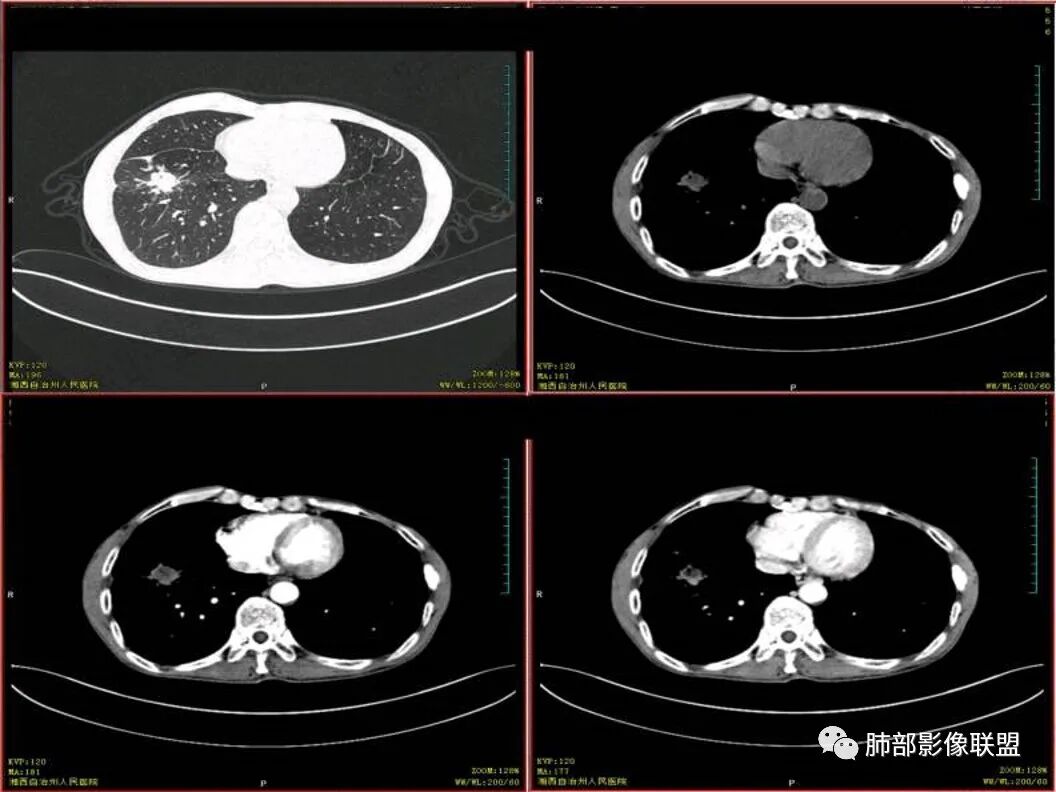

cyfra21-1是细胞角蛋白19的可溶性片段,被认为是一种主要用于检测肺癌的肿瘤标志物,尤其对非小细胞肺癌的诊断具有重要价值。肺癌组织中,CYFRA21-1 含量丰富,尤其是在肺鳞癌中有高表达。肺炎、肺结核、肺气肿、哮喘等疾病一般不引起CYFRA21-1升高。良性肝病、肾衰竭可引起轻微升高,但很少超过10ng/ml。CYFRA21-1的血清水平与年龄、性别、吸烟与否和妊娠等无关。如果肺部存在不清晰的环形阴影,同时血清CYFRA21-1浓度>30ng/ml,原发性支气管肺癌的可能性非常高。

中年男患,亚急性起病,既往有结核相关病史,辅助检查CRP高于正常,血沉稍高,CYFRA21-1偏高。

影像表现为 双肺上叶多发索条斑片影,可见支气管牵拉性扩张,考虑为陈旧肺结核纤维硬结灶。右肺下叶前基底段团块影膨隆生长,边界不清,呈分叶,毛刺,胸膜牵拉,支气管截断,中央区坏死明显,但未形成空洞,坏死区边缘光整,不均匀环形强化,隐约见壁结节。纵隔淋巴结肿大伴钙化,病灶远端见阻塞性炎症,结合CYFRA21-1偏高,应想到考虑恶性病变,鳞癌可能性大。

鳞癌的影像特点:

鳞癌的坏死特点

1. 坏死明显,范围大,多,散在

2. 坏死的边界清楚,坏死较彻底,“湖泊样”

3. 病理原因:巢团状生长,中央部分血供不足,并挤压破坏肺血管

4. 壁结节多,是坏死区融合的结果

5. 空洞位于远侧的原因:周围区坏死重

6. 周围区坏死壁常很薄